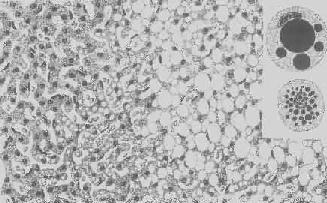

形态学:轻度肝脂肪变性时,肝肉眼观可无明显改变,或仅轻微黄染。如脂仿变性比较显著和广泛,则肝增大,色变黄,触之质如泥块并有油腻感。镜下,肝细胞内的脂肪空泡较小,起初多见于核的周围,以后变大,较密集散布于整个胞浆中,严重时可融合为一个大空泡,将细胞核挤向胞膜下,状似脂肪细胞(图1-18)。脂肪变性在肝小叶中的分布与其病因有一定的关系,例如肝淤血时,小叶中央区缺氧较重,故脂肪变性首先在此处发生。但长期淤血后,小叶中央区的肝细胞大多萎缩、变性或消失,于是小叶周边区肝细胞也因缺氧而发生脂肪变性。磷中毒时,肝细胞脂肪变性则主要发生于小叶周边区,这可能是由于此区肝细胞对磷中毒更为敏感的缘故。

图1-18 肝细胞脂肪变性

肝细胞胞浆内出现大小不等的脂肪空泡;右上角为饿酸染色的脂肪细胞, 脂滴染成黑色